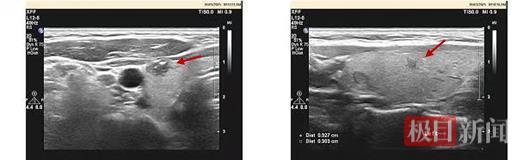

经过多方打听和慎重考虑,孙女士来到武汉大学人民医院乳腺甲状腺外科陈创教授团队李智宇医生的诊室。当超声科吴田医生为她再度检查时,却发现其双侧甲状腺多发结节:右侧腹侧边缘最大直径0.9厘米的结节高度怀疑恶变,左侧一直径0.3厘米的结节也高度怀疑有风险,而右侧颈Ⅲ、Ⅳ区淋巴结的钙化灶,更是一道危险的预警信号。

右侧腹侧及左侧甲状腺结节